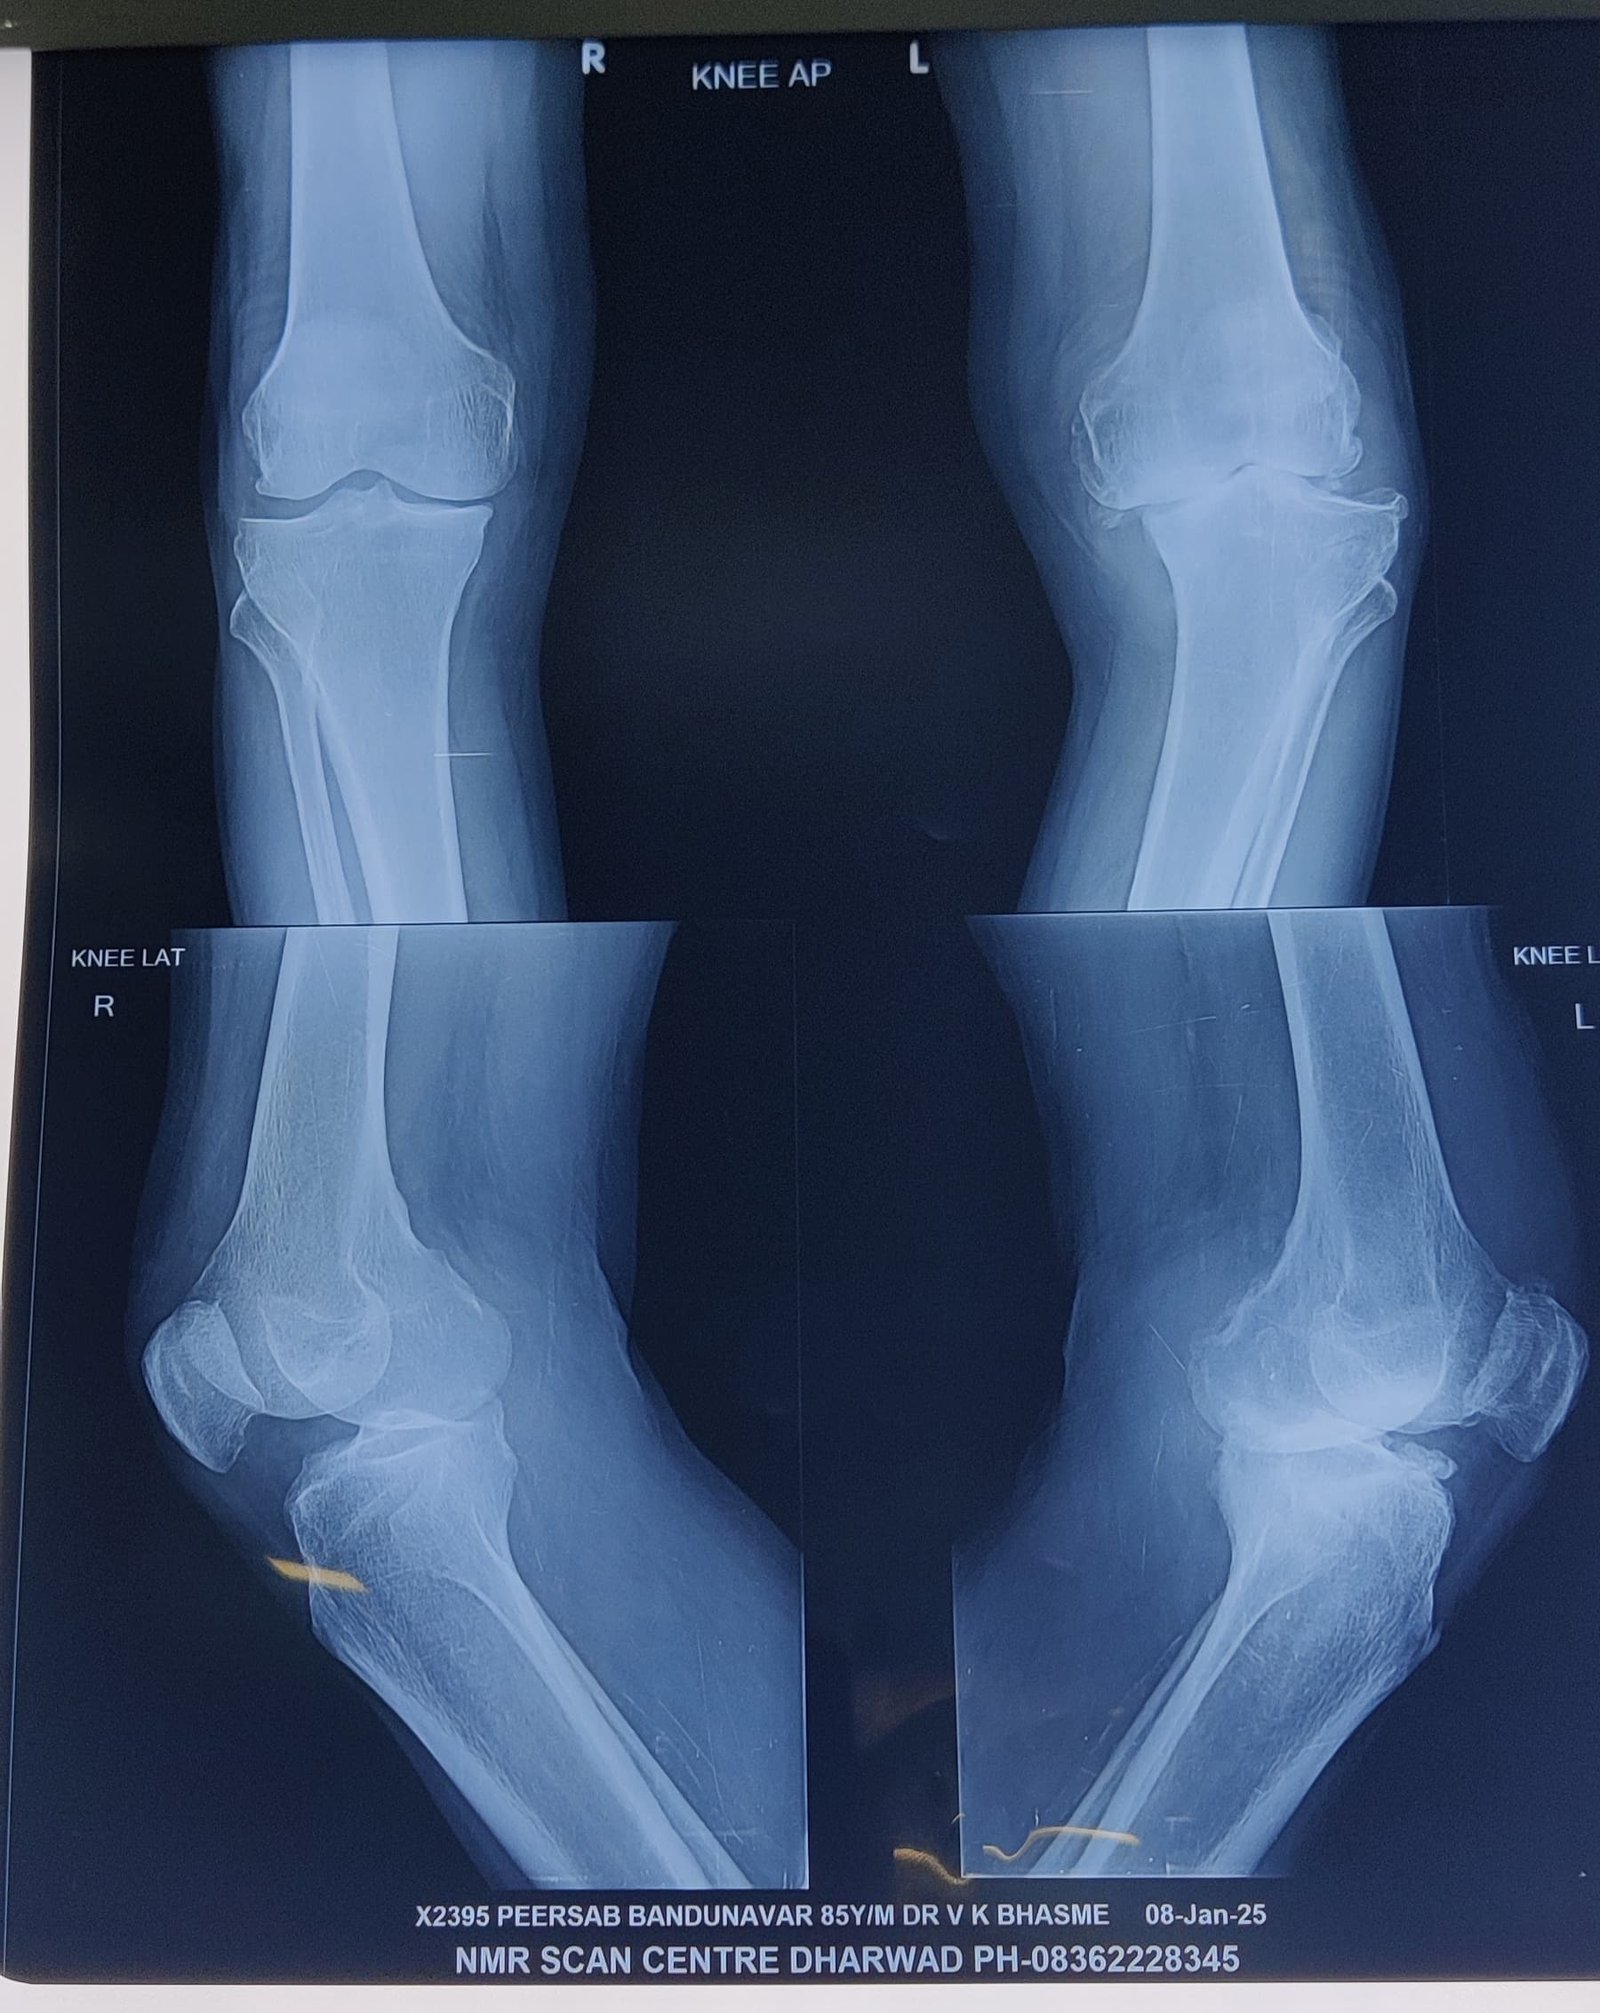

68 years lady was not walking for 5 years 8 months